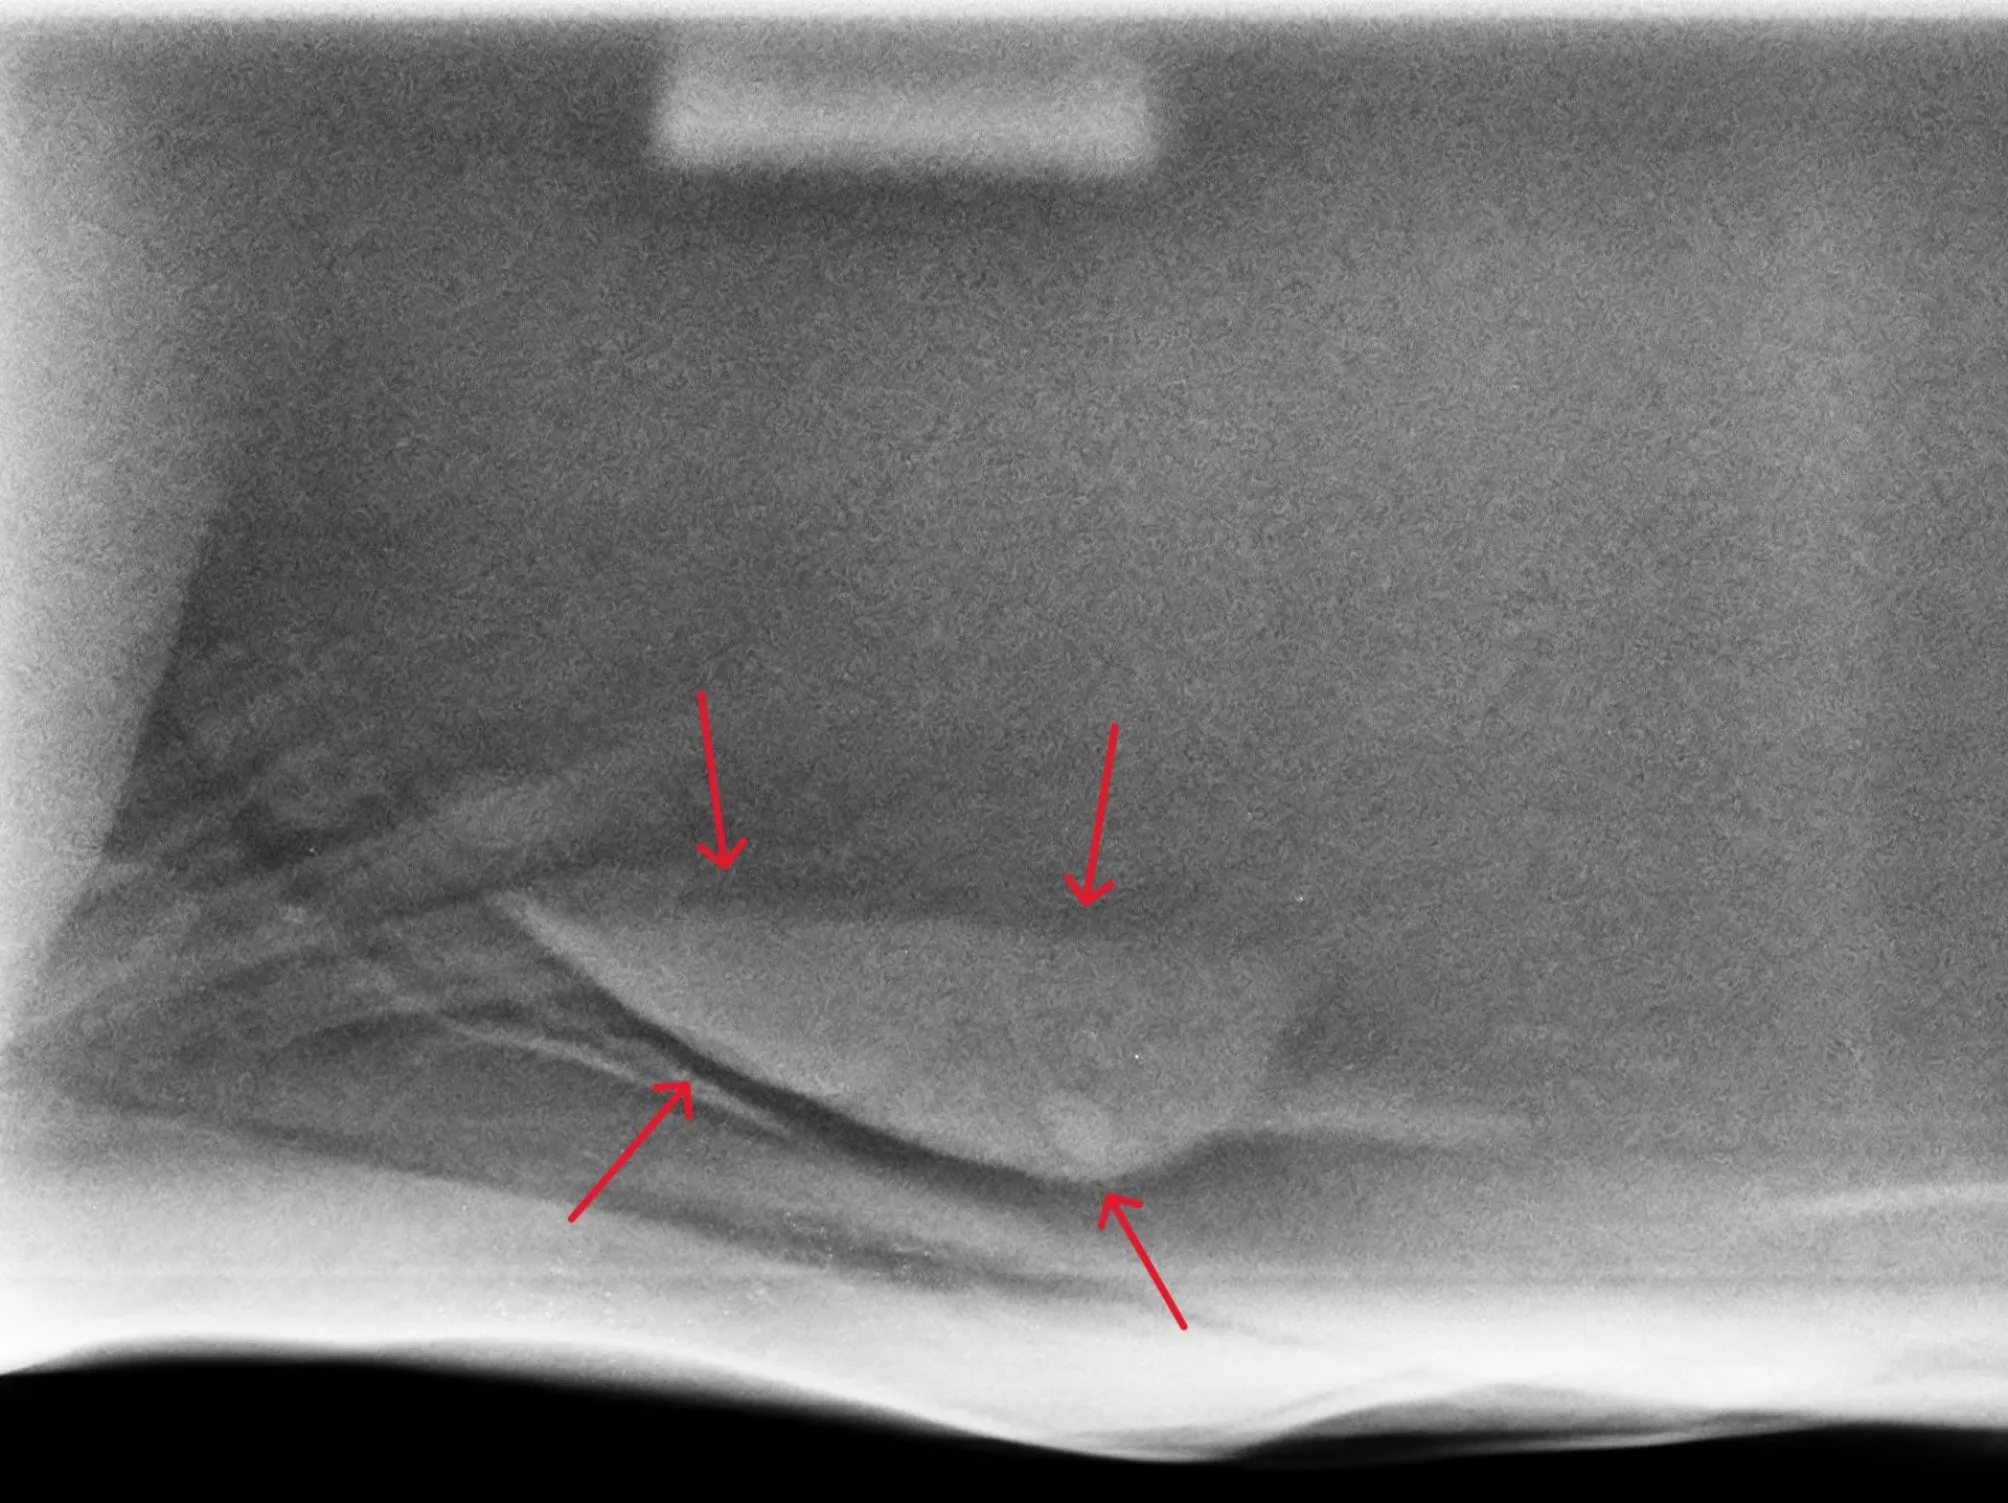

You may commonly see your veterinarian auscultate your horse for sand (listen to its abdomen with a stethoscope). When sand is moving within the digestive system, it sounds like ‘waves on the beach’, which is what we are listening for! It is important to note, however, that auscultation can only confirm if sand is present and cannot be used to completely rule out the presence of sand. We have seen many cases where no sand is auscultated; however, we know the horses are full of sand, and it has been confirmed on radiographs.

The best way to diagnose sand is abdominal radiographs, which can confirm the presence of sand and also the quantity of sand. These can be performed at your dental appointment, please just let us know at your appointment.

This information can then be used to formulate an appropriate treatment plan. Before-and-after radiographs can also help determine the success of a treatment plan and ensure the sand has actually been removed.